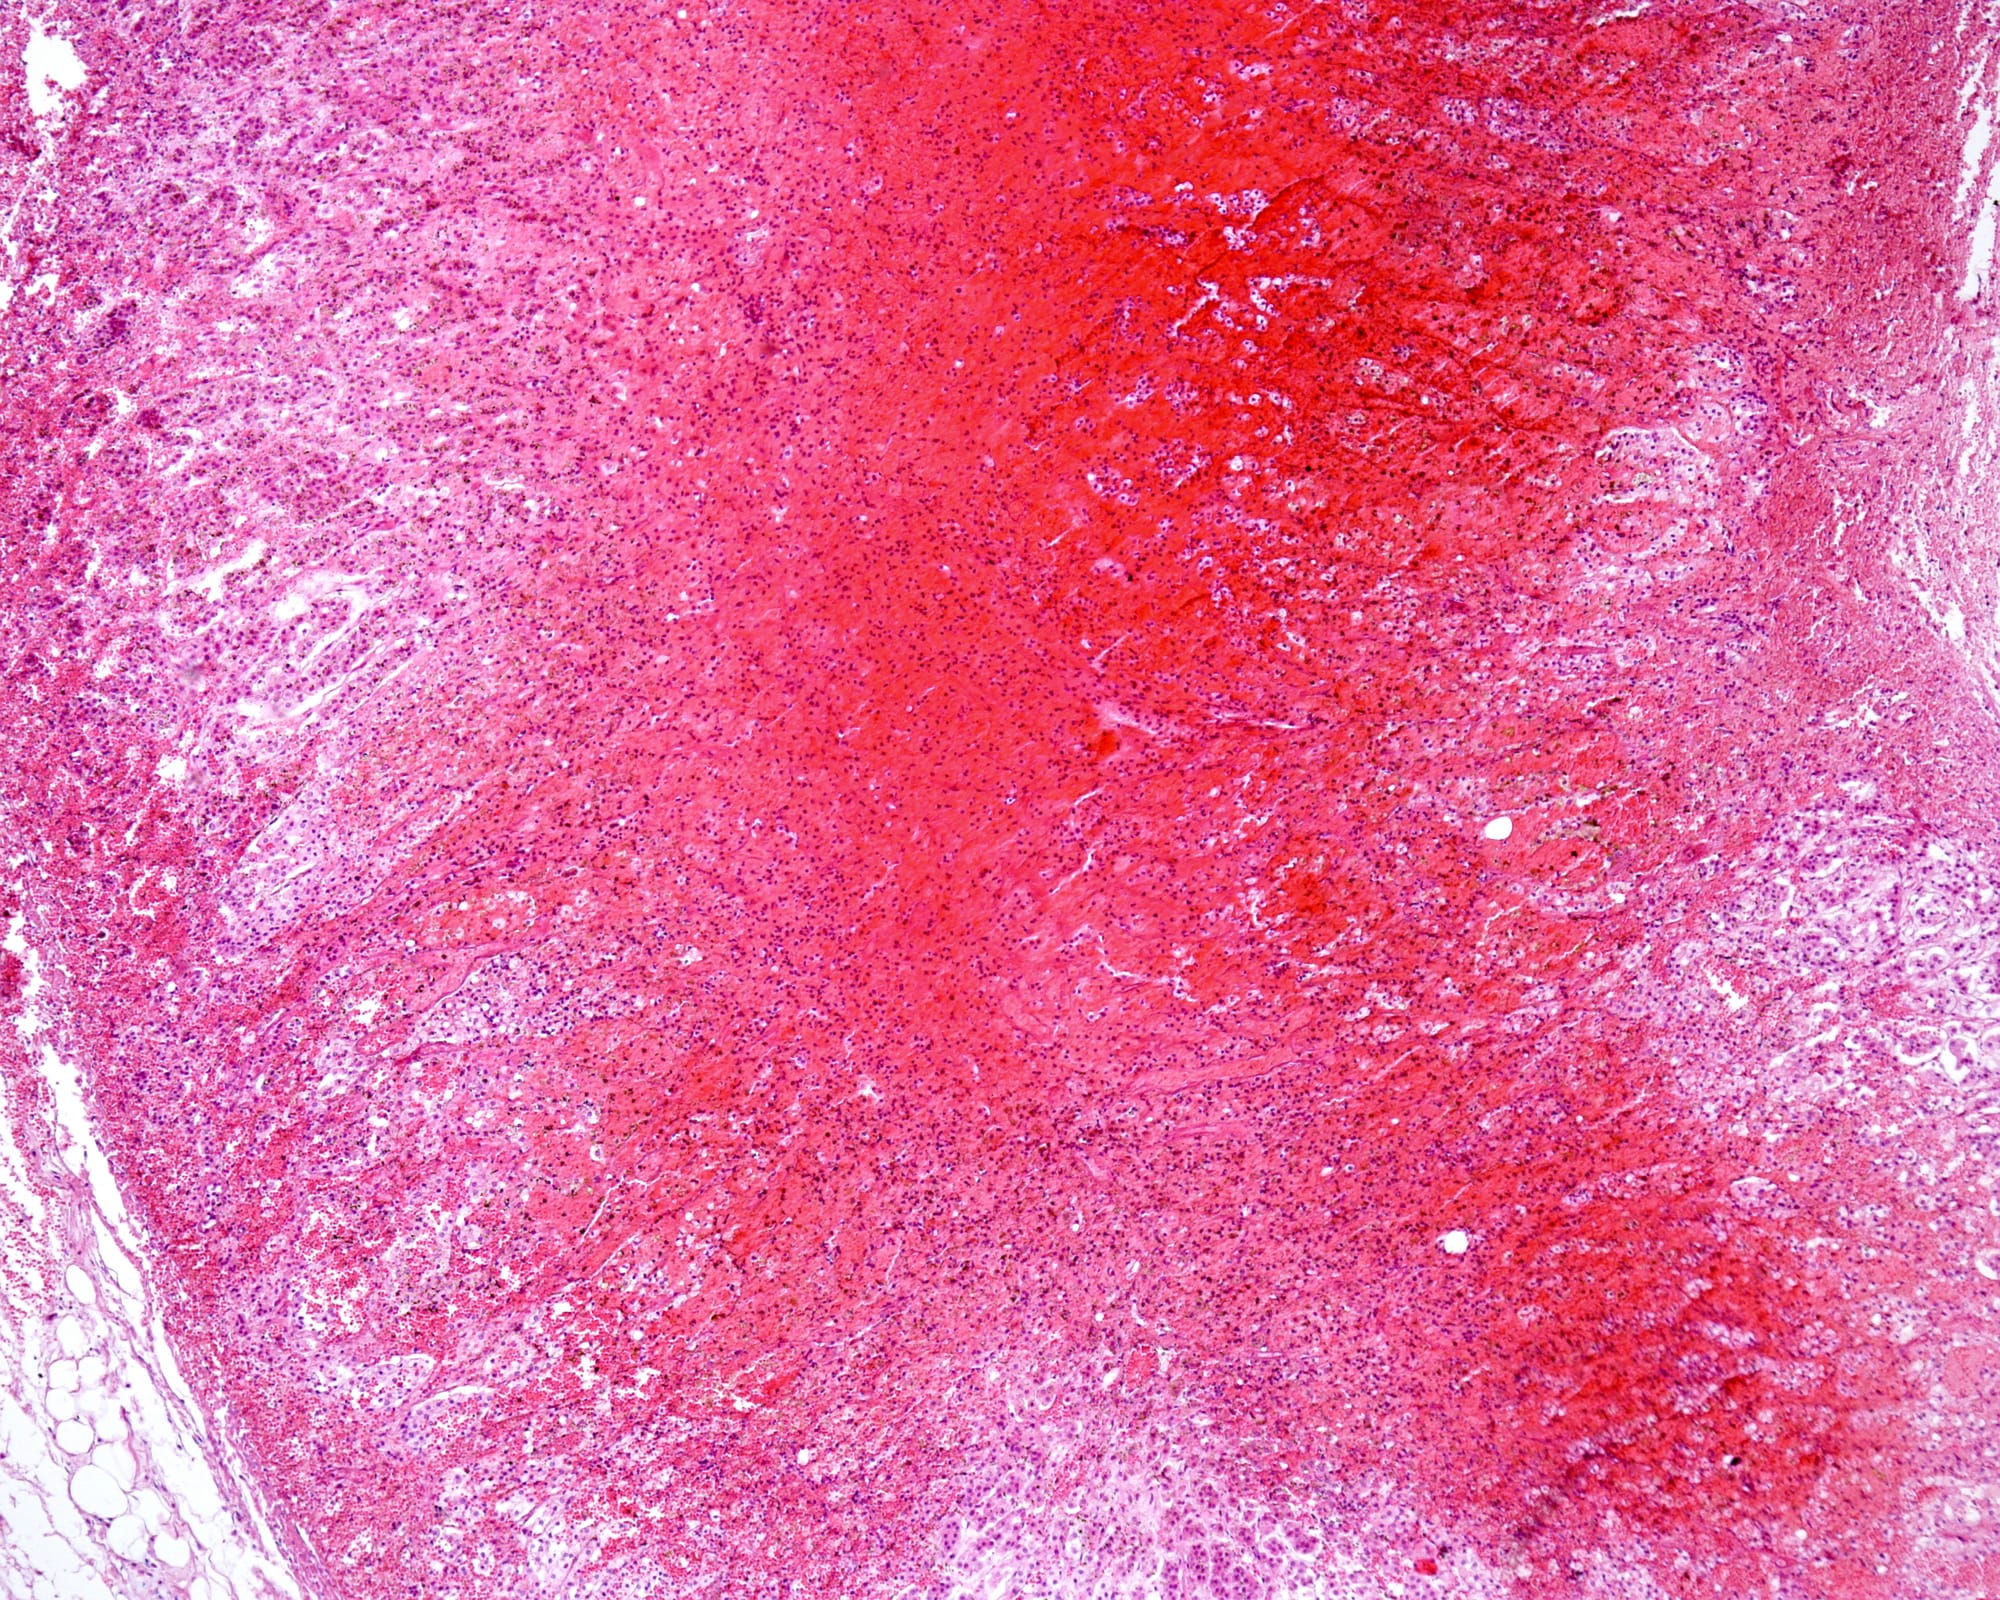

Acute scrotum in neonates is a rare condition with multiple causes, including incarcerated hernia, testicular torsion, birth trauma, gross hydrocele, and neonatal adrenal haemorrhage, the least common aetiology. Early diagnosis and intervention are essential to prevent testicular ischemia. Due to the continuity between the retroperitoneum and the scrotum via the processus vaginalis and inguinal canal, blood from an adrenal haemorrhage may track down into the scrotum, leading to swelling and discoloration. We report a case of a 1-day-old male neonate born via emergency caesarean section at 37 weeks due to foetal distress. The baby initially admitted to the NICU for transient tachypnoea, developed a right hemi-scrotal swelling with bluish discoloration on the second day of life. Scrotal ultrasound suggested testicular torsion, but Doppler imaging showed absent blood flow. Further abdominal ultrasound confirmed a right adrenal haemorrhage. The neonate was managed conservatively with intravenous fluids, antibiotics, oxygen support, and coagulation management. Serial ultrasounds showed gradual resolution, and he was discharged on the 17th postnatal day. Follow-up at 1 and 3 months showed complete recovery with normal growth. Neonatal adrenal haemorrhage should be considered in cases of acute scrotum, especially in neonates with birth asphyxia. Abdominal ultrasound can aid in diagnosis, preventing diagnostic delays, unnecessary surgery, and anaesthesia exposure. This case highlights the importance of thorough imaging and awareness of rare differential diagnoses, contributing to improved clinical practice and better neonatal outcomes.